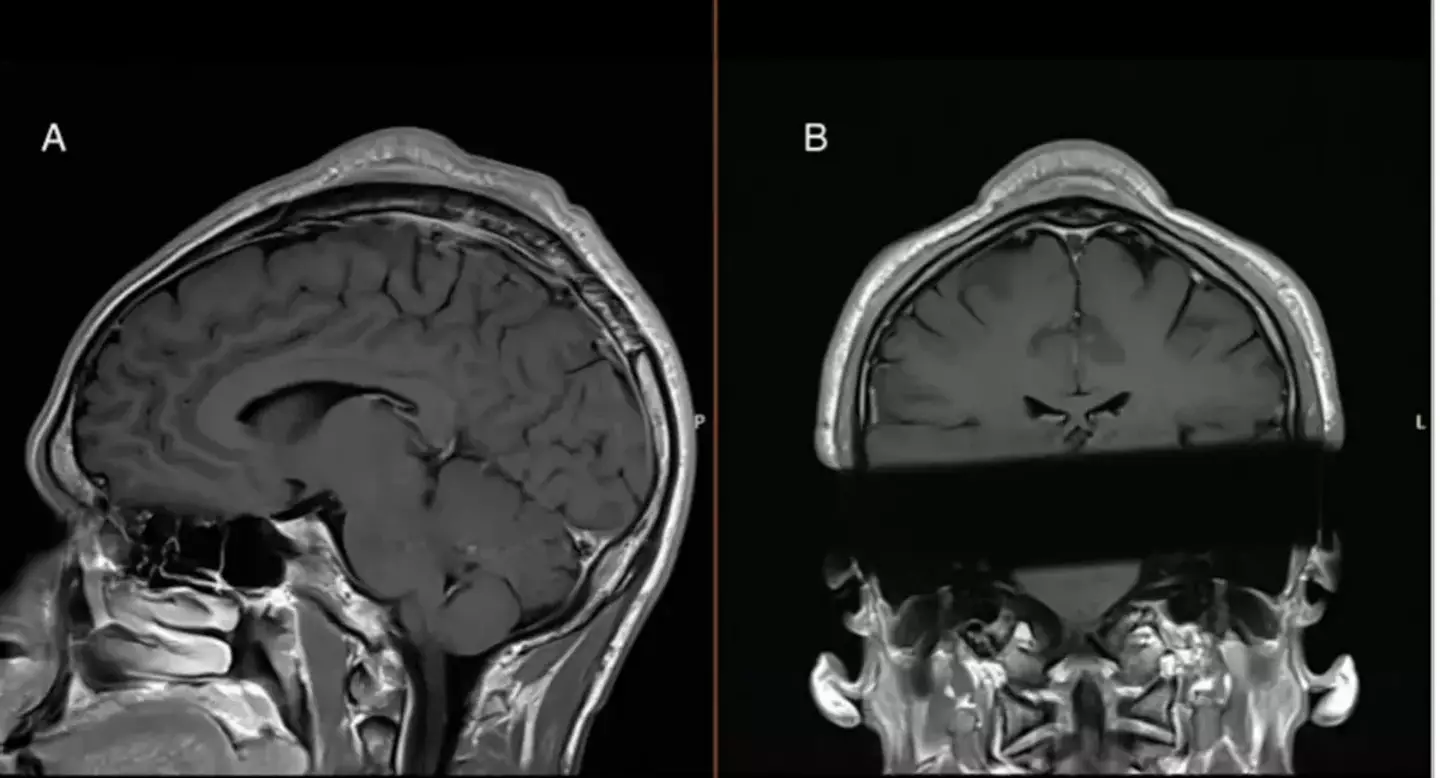

One particular case was posted online, showing an MRI image of a breakdancer who developed a 'headspin hole' after years of performing the move.

The image quickly went viral on X (formerly Twitter), reaching over 115,000 views as users reacted to the protruding bump visible on the dancer's head.

MRI scans revealed thickening in the subcutis, the deepest layer of skin, which led to the formation of a noticeable 'cone-head' shape at the top of his scalp.